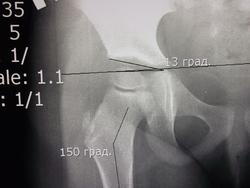

Первоначально обратились с жалобами на боли в левой ноге возникающей утром, в течении 3-х месяцев. В клинической картине походка не нарушена, отмечается укорочение левой ноги 0,5см., приводящяя контрактура бедра, гипотрофиии нет. Вальгусная деформация коленных суставов и стоп. Смущает возраст и пол ребенка. Выставил диагноз Болезнь Пертеса.

Возраст девочки 3года 6 месяцев. УЗИ тазобедренных суставов( 02.03.13)- признаки болезни Пертеса.

Похоже, болезнь Пертеса.